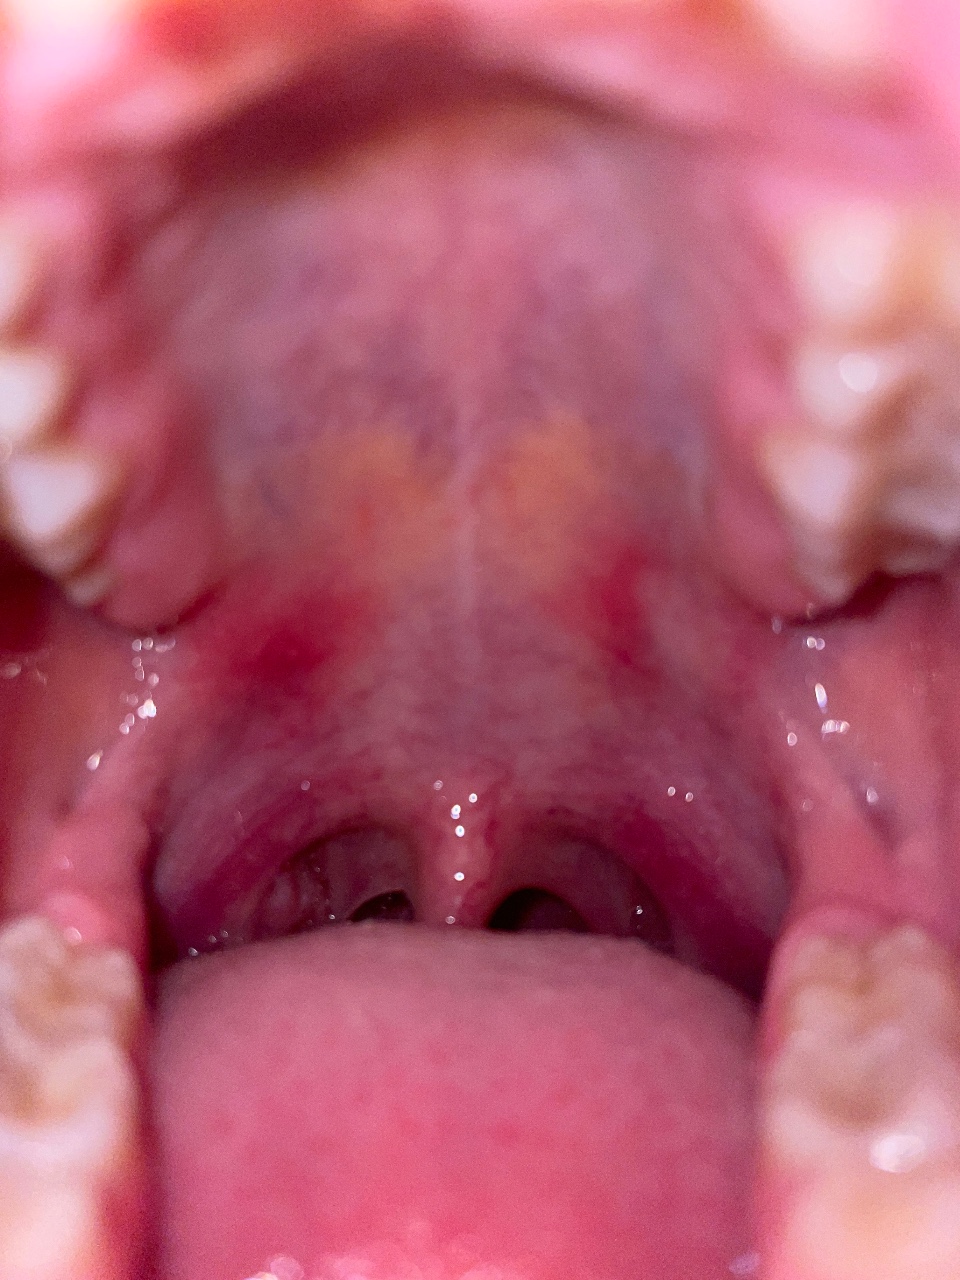

Красные пятна на нёбе, дискомфорт при глотании

Здравствуйте, у меня сегодня начало болеть нёбо и появились красные пятна на нем, также появился дискомфорт при глотании. Недавно переболела ОРВИ. Подскажите пожалуйста что это такое и чем можно вылечить?